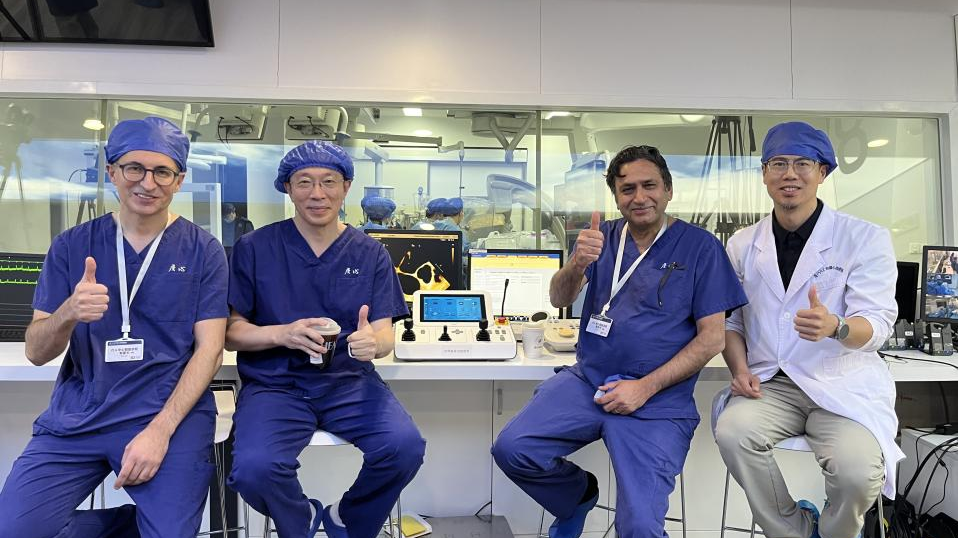

近日,美国Cedars-Sinai医学中心的顶尖心脏病学专家Raj Makkar教授和Hasan Jilaihawi教授跨越重洋,专程到访厦门大学附属心血管病医院(简称“厦心”),观摩王焱教授团队开展了多例机器人辅助经导管二尖瓣修复术,中国科学院院士、复旦大学附属中山医院葛均波教授,台湾知名心外科专家、台北振兴医院院长魏峥教授亲临现场,全程指导了本次手术的第一例。此次手术应用的是上海术济客医疗科技有限公司与厦心医院医工结合自主研发的机器人辅助系统。

本次再次吸引来院观摩的Raj Makkar教授是世界知名的介入心脏病专家,在全球TAVR手术数量位居前列,并且在美国完成了最多TEER(MitraClip)操作,对于未来将机器人辅助系统应用到瓣膜介入手术领域充满兴趣和信心。本次机器人辅助瓣膜介入手术交流标志着中美顶尖心脏团队在微创心脏瓣膜修复领域实现技术交融与协同实践,开创了该领域国际合作的新高度。

手术圆满完成后,参与此次手术的美国专家及葛均波院士、魏峥教授等心血管领域权威人士,对机器人辅助二尖瓣系统的术中表现和产品未来延展性给予高度认可。专家们一致认为,该系统的临床应用显著提升了二尖瓣反流手术的安全性与精准性,尤其在复杂病例的处理上展现出超越传统术式的显著优势,堪称心血管介入治疗领域的一项重要突破。同时,专家团队也基于手术实操经验,提出了前瞻性改进建议。术济客医疗将与专家团队建立长期深入合作,以临床反馈为导向持续优化系统功能,推动机器人辅助医疗技术迈向更高水平,为心血管疾病的精准治疗持续赋能。

Raj Makkar教授